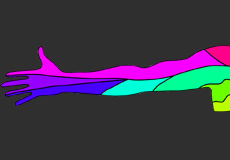

Arm Pain of Spinal Origin

Arm pain of spinal origin can be described as discomfort or pain felt anywhere in the arm including the wrist, elbow, or shoulder as a result of a pinched nerve (nerve compression) or irritated nerve in the spinal cord. The pain can occur as a dull constant pain or a sudden sharp pain that can develop suddenly or over time. The pain may be confined to one area of the arm or may radiate to other areas of the arm such as the hand, wrist, elbow, or shoulder.